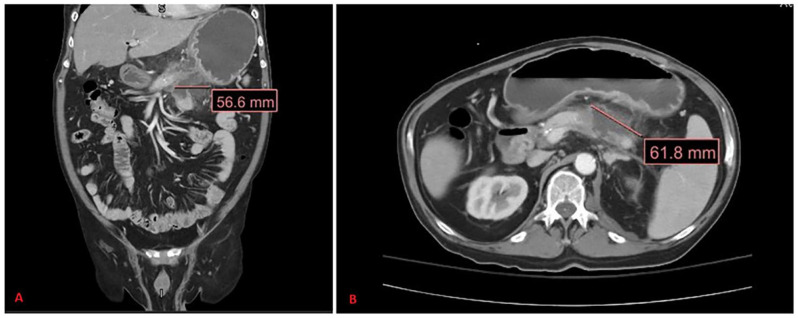

当首次出现时,心电图上的st段抬高需要仔细检查。最令人关注的可能诊断是急性冠状动脉综合征,但它并不是唯一的临床实体,可引起st段抬高。在此,我们报告一例62岁男性吸烟者,既往有未控制的糖尿病、高血压和高脂血症病史,腹痛持续1周。入院时心电图显示st段抬高;然而,他的临床表现,没有心绞痛症状,床边经胸超声心动图正常,肌钙蛋白范围正常,都不是心肌梗死的指示。事实上,他被发现脂肪酶升高,CT结果与急性胰腺炎一致。这个病例强调了一个罕见的胰腺炎的表现,并说明了在评估患者时获得全面的临床病史的重要性,以确保患者得到有效和适当的护理。

When first presented, ST-segment elevation on EKG (electrocardiogram) requires close scrutiny. The most concerning of possible diagnoses is acute coronary syndrome, yet it is not the only clinical entity that can cause ST-segment elevation. Herein, we present a case of a 62-year-old male current smoker with past medical history of uncontrolled diabetes, hypertension, and hyperlipidemia presenting with abdominal pain for 1 week duration. His initial admission EKG illustrated ST-segment elevation; however, his clinical presentation, lack of anginal symptoms, normal bedside transthoracic echocardiogram, and normal range troponin were not indicative of myocardial infarction. In fact, he was found to have elevated lipase and CT findings consistent with acute pancreatitis. This case highlights an uncommon presentation of pancreatitis and illustrates the importance of obtaining a comprehensive clinical history when evaluating patients to ensure patient's receive efficient and appropriate care.